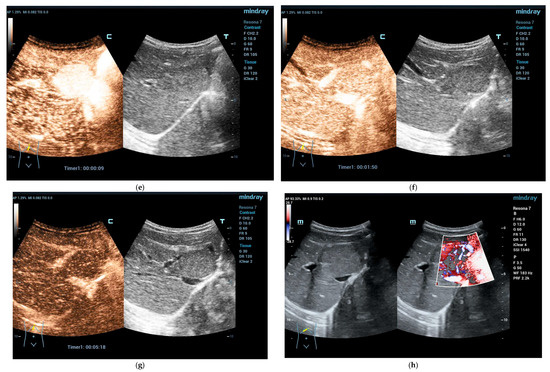

4.3.1. Hepatic Hemangioma

4.3.2. Congenital Hepatic Hemangioma

4.3.3. Infantile Hepatic Hemangioma

4.4. Vascular Malformations Other than Hemangioma

Focal Nodular Hyperplasia (FNH)